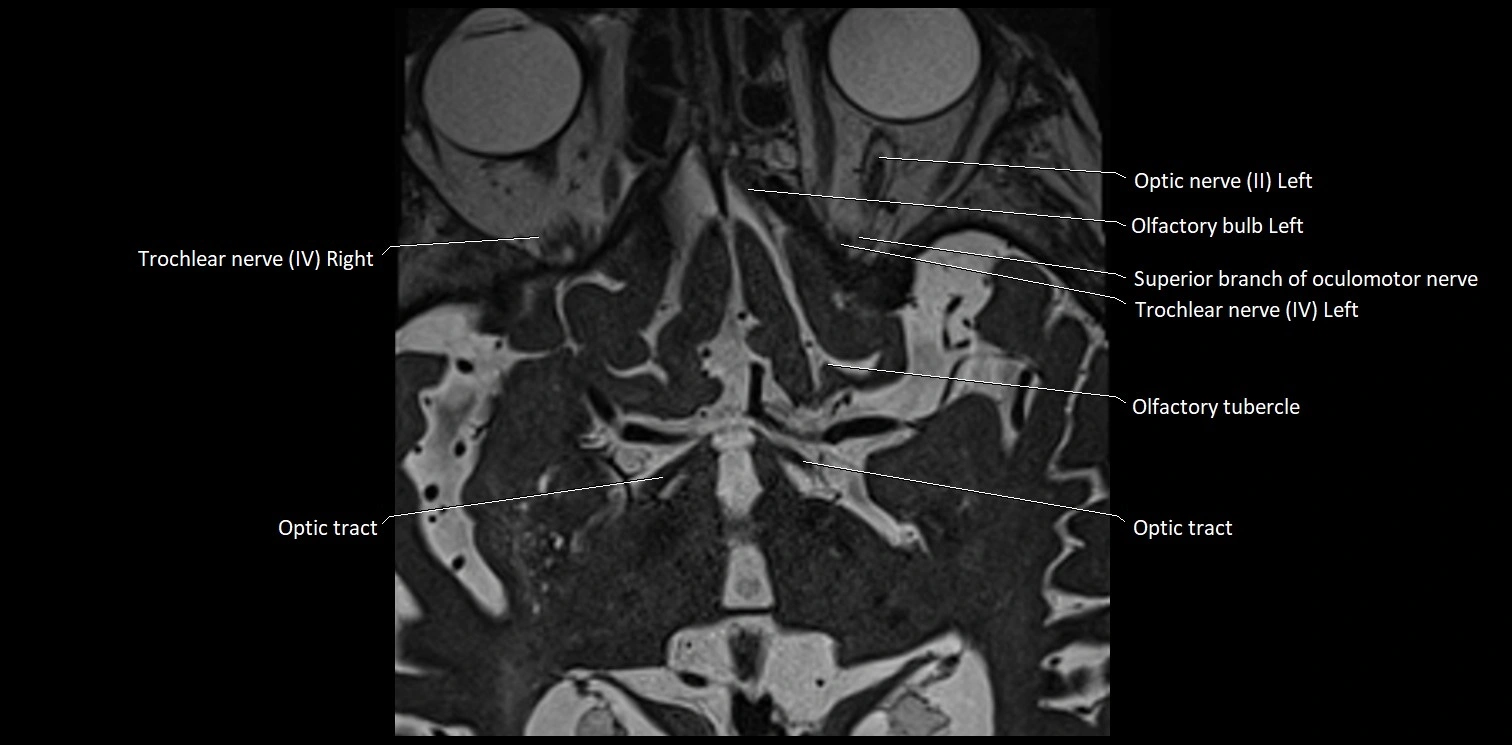

MRI Appearance

• The abducens nerve is a small, thin, linear structure

• Best visualized on high-resolution T2-weighted 3D MRI sequences (e.g., FIESTA or CISS)

• Seen as a hypointense (dark) line running from the brainstem at the pontomedullary junction, traversing the prepontine cistern, and entering Dorello’s canal under the petrosphenoidal ligament, then into the cavernous sinus, and finally the orbit

• May be challenging to visualize in standard MRI due to its small size

• Pathology may be inferred by absence, displacement, or enhancement of the nerve

MRI images

image